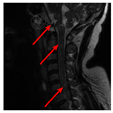

患者 女,55岁,因"畏寒发热4 d"于2017年11月13日在家人搀扶下步入中国医科大学人民医院急诊科就诊。患者发病前4 d曾有受凉发热史,体温最高达39 ℃,伴咳少量白色粘痰。既往体健,无近期疫苗接种史,否认外伤史、冶游史及自身免疫性疾病史。急诊体检:体温39.6 ℃,双肺呼吸音粗,心律齐,心率106次/min,腹部无压痛;意识清楚,颅神经未见异常,双侧巴宾斯基征阴性,颈软。肺CT扫描显示:双肺纹理紊乱,肺内散在小结节及陈旧性病变,未见明显急性炎症改变(图1A)。血液常规显示白细胞计数正常,中性粒细胞比例78.9%(↑),C反应蛋白正常。以"发热待查"收入呼吸内科住院。入院后给予头孢西丁抗炎和物理降温治疗,体温波动于38.3~41.1 ℃,并相继出现排尿、排便困难。入院1周后病情继续进展,表现为咳嗽无力、呼吸困难,以至呼吸衰竭、精神萎靡,复查肺CT显示双肺下叶模糊淡片影,右肺下叶不张可能性大,双侧胸腔积液,考虑与吸入性肺炎有关(图1B)。因患者呼吸困难继续加重,故转入ICU病房,行药物治疗的同时予以呼吸机辅助通气。期间患者体温仍持续在38 ℃以上,并反复达40 ℃,故在给予抗菌素治疗的同时又相继给予奥司他韦、更昔洛韦抗病毒治疗,并更换静脉抗菌素为万古霉素1500 mg/d、泰能4 g/d。但患者仍持续高热不退,期间多次进行血液常规化验,显示白细胞总、分数均轻度异常或正常;降钙素原0.07 ng/mL(参考值<0.05 ng/mL);肝肾功能、甲功五项、凝血功能、乙丙型肝炎、肿瘤标志物未见异常。血液病原微生物学检查:布氏杆菌、人类免疫缺陷病毒、巨细胞病毒IgM、单纯疱疹病毒IgM、军团菌IgM、柯萨奇病毒IgM均为阴性,支原体抗体滴度、肥达氏反应和外斐氏反应均无异常。免疫学检查:抗中性粒细胞胞浆抗体(-);抗核抗体谱(15项)中抗SS-A抗体(±)、抗Ro-52抗体(±);血沉、风湿三项、血IgA、IgG、IgM、IgE及血清蛋白电泳均未见明显异常。血培养:未见需氧、厌氧菌生长。痰涂片:无细菌、结核杆菌生长。尿常规、尿沉渣定量无异常。心脏超声、全腹CT扫描无异常。入院第11天(2017年11月24日)因停用镇静药物后患者仍呼之不应,急请神经内科会诊。脑脊液检查:脑脊液压力160 mmH2O(1 mmH2O=0.098 kPa),外观无色透明;脑脊液常规:白细胞总数352×106/L(↑),未见红细胞;脑脊液生化:糖2.34 mmol/L(↓)、蛋白质0.78 g/L(↑)、氯化物正常;细菌及结核杆菌涂片(-)。血液及脑脊液水通道蛋白和脑脊液寡克隆带未检测。因患者脑脊液白细胞总数增高较明显,故给予抗菌素治疗的同时给予静脉甲泼尼龙(500 mg/d、连续4 d,后逐渐减量)治疗。激素治疗的第2天患者体温开始下降,第5天降至正常,第9天自主呼吸明显恢复,但仍咳痰无力。在患者呼吸困难、发热症状好转的同时,也发现患者存在四肢瘫痪(双上肢肌力Ⅱ级、双下肢肌力Ⅰ级)。为进一步明确肢体瘫痪原因,入院4周后(2017年12月7日)行头颅MRI平扫,显示脑干、双侧丘脑、双侧小脑半球、双侧半卵圆中心、侧脑室旁及基底节区多发、不对称的异常信号(图2)。2017年12月14日颈段MRI平扫显示:延髓与颈髓交界、C1~T1节段间多发、不连续的髓内异常信号(图3)。结合患者发热、亚急性起病过程,尽管脑脊液呈炎性改变,但给予抗病毒、抗细菌治疗效果不佳,并结合中枢神经系统影像学改变,即颅内及脊髓均有受累,支持中枢神经系统脱髓鞘性疾病的诊断。2017年12月24日患者自主呼吸完全恢复,此期间排便功能及肌力也逐渐恢复,于2017年12月28日转回呼吸内科病房。出院后随访3个月,患者仍处于恢复中,双上肢肌力Ⅴ-级、双下肢肌力Ⅳ级,因遗留排尿困难仍予留置导尿管。

延髓与颈髓交界、C1~T1节段间多发、不连续的点片状长T2WI髓内信号(箭头所示)

ADEM病变主要累及脑和脊髓的白质,MRI对其诊断具有重要意义,一般表现为侧脑室旁及额颞顶枕白质区内多发的点片状病灶,部分可见"垂直脱鞘征";同时也可见于灰质,后者以基底节区、丘脑、脑干多见。ADEM的脑部病灶多在T1WI呈低或稍低信号,在T2WI和FLAIR呈高信号,多双侧不对称,形态可呈圆形、椭圆形或不规则,直径多为1.0~2.0 cm或略小;脊髓病灶主要位于颈、胸髓髓内,表现为连续或节段性的长条形信号,长度可达3~4个脊椎节段,T1WI上呈低信号,T2WI上呈高信号,信号多较均匀,脊髓无增粗,且无特异性[3,4]。除中枢神经系统影像学改变外,ADEM的诊断还需符合以下标准:(1)急性起病,首次因可疑中枢神经系统炎性脱髓鞘而表现出多灶性神经功能缺损;(2)排除中枢神经系统感染、结缔组织病、遗传代谢性疾病及肿瘤;(3)发病3个月后没有新的临床表现和MRI改变[1,5,6,7]。本例患者的中枢神经系统影像学改变和临床表现均符合ADEM的诊断标准,但该患者发病时无确切的局灶性神经功能缺损表现,并且其后因给予呼吸机通气并镇静也影响了对神经系统体征变化的观察,包括对呼吸衰竭、四肢瘫痪及尿潴留原因的分析不足,导致未能早期及时诊断。